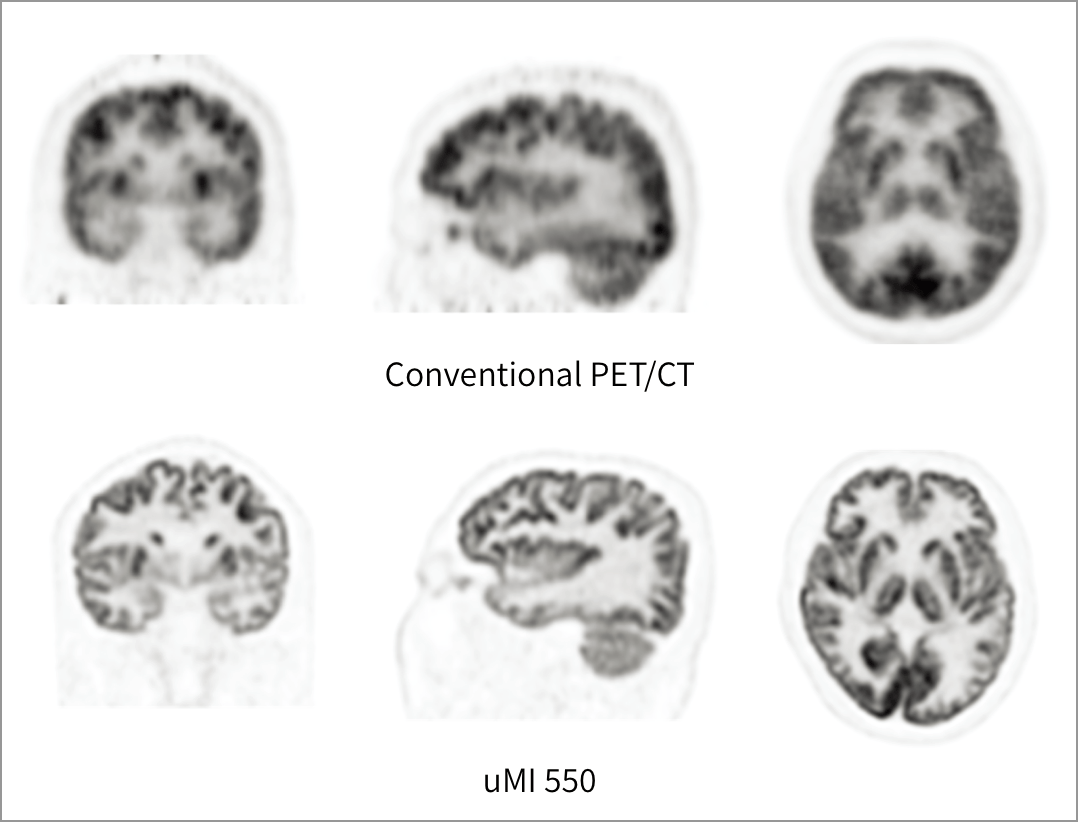

Creier

Imagistica prin PET/CT digital permite vizualizarea detaliată a structurilor cerebrale, fiind esențială în diagnosticul și monitorizarea afecțiunilor neurologice și în detectarea leziunilor de mici dimensiuni.